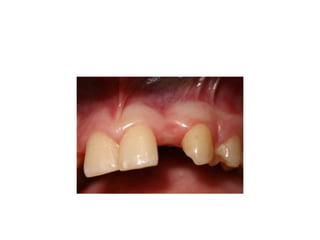

palatal inflammation is noted from

retainer